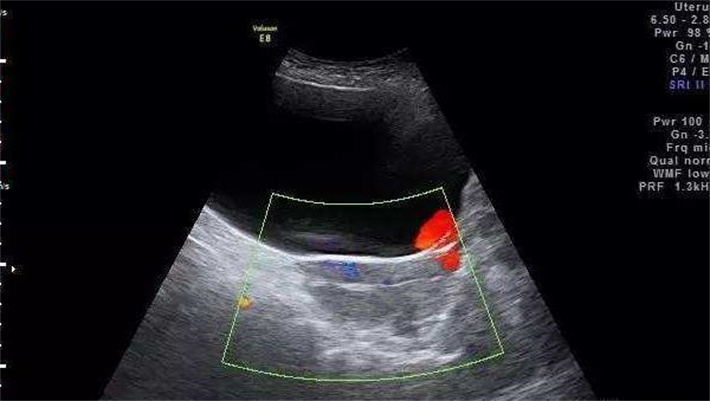

女方的生殖系统检查也相当重要,阴道B超可以直观地查看子宫和卵巢的形态、大小,有无子宫肌瘤、卵巢囊肿等病变,了解子宫内膜的厚度和形态,判断是否适合胚胎着床。输卵管造影则能确定输卵管是否通畅,虽然试管婴儿是将胚胎直接移植到子宫内,但输卵管的健康状况也可能间接影响盆腔环境和激素水平,进而对试管结果产生潜在影响。